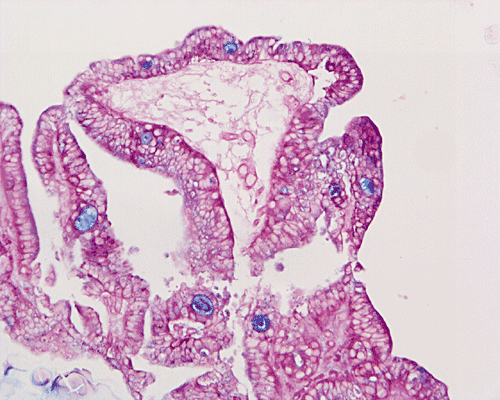

A. B. C. D. E.

PAS-Alcian blue

Mucicarmine

On scanning-magnification, the biopsy material consists of small nodules of stromal tissue with epithelium lined papillae (Panel A). On low-magnification (Panel B), both multilayered epithelium  and cribiform pattern (Panel C)are demonstrated. On high-magnification  (Panel D), the epithelial cells are hyperchromatic and pleomorphic. Intracytoplasmic mucin is well demonstrated by periodic acid-Schiff (PAS)- Alcian blue stain (Panel E) and mucicarmine stain (Panel F). No invasion is demontsrated.

Histologically, in situ adenocarcinoma is defined as a noninvasive glandular lesion, where the mucosa of the urinary bladder is replaced by an atypical, often pseudostratified columnar epithelium, featuring atypical cytoplasm and definitive cytologic atypia with nuclear hyperchromasia, moderate to severe nuclear pleomorphism, frequent mitosis and apoptosis 4. Necrosis is infrequently seen.

Three distinct architectural patterns have been described: papillary, cribriform and flat 2, 3, 4. Papillary architecture is the one most commonly seen, followed by cribriform pattern. Individual cases rarely show a pure pattern; rather, various combinations of the three patterns are more often seen.